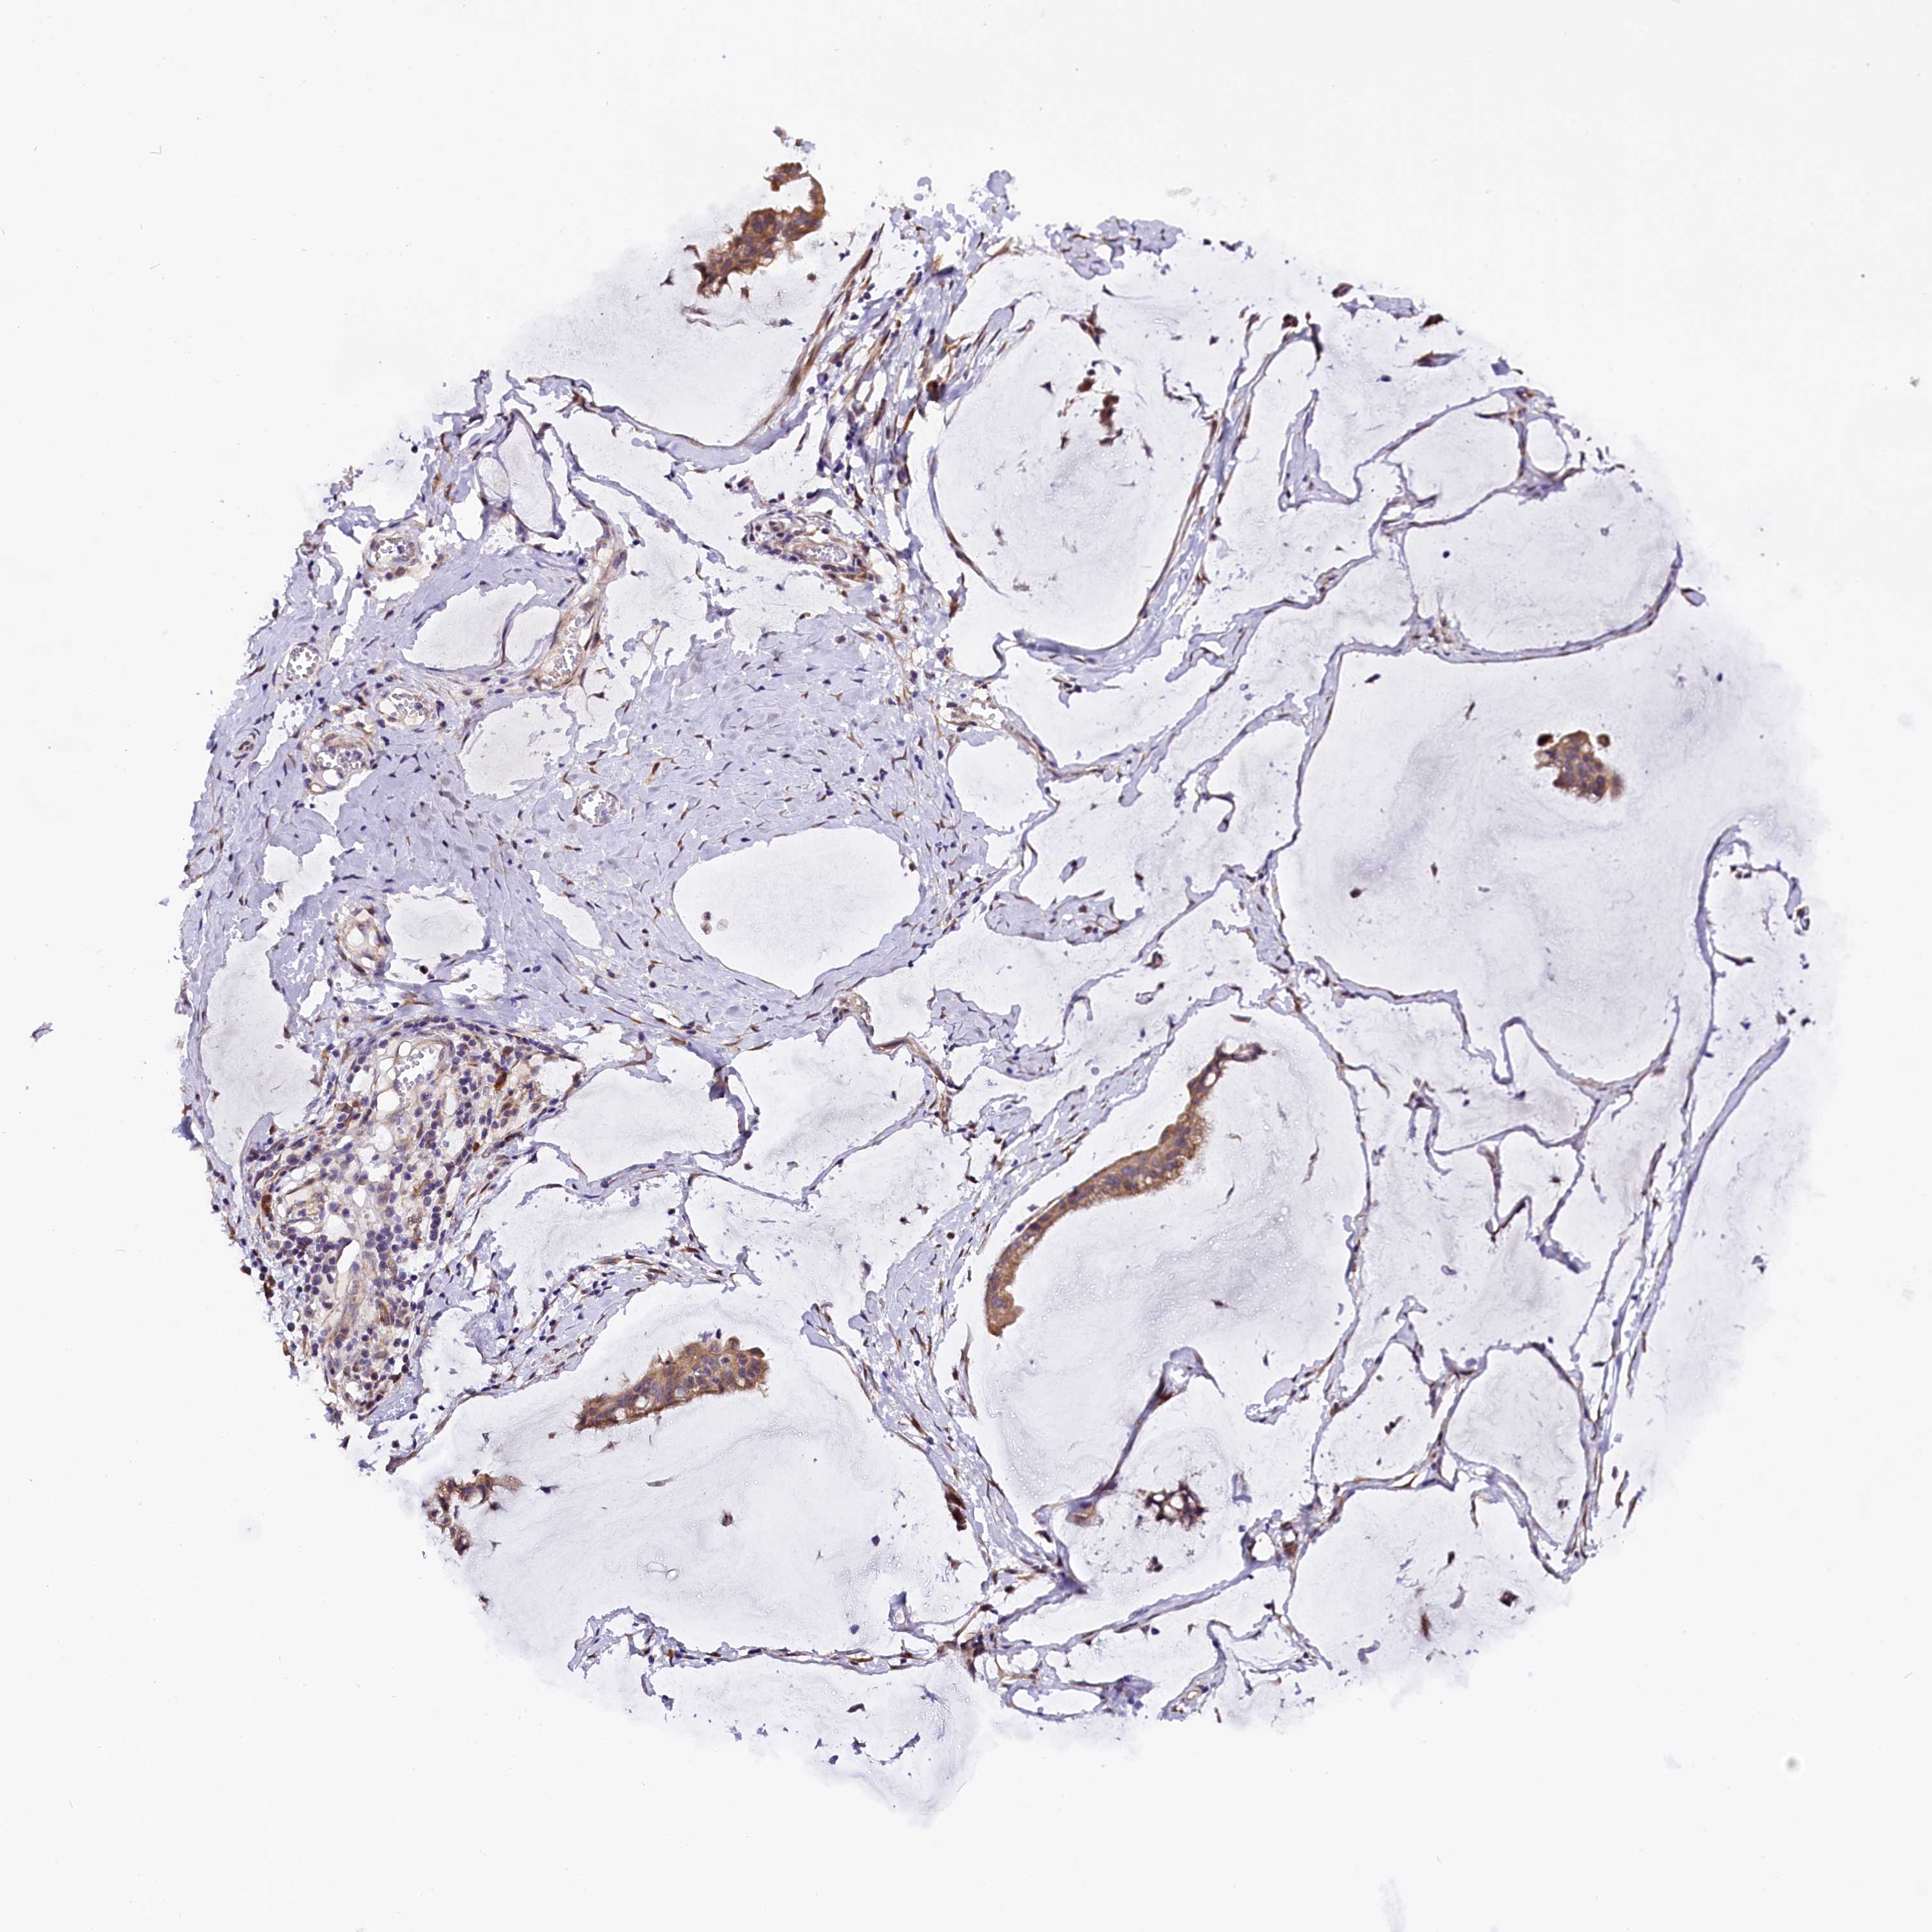

OVARIAN CANCER - Protein expressioni

A mouse-over function shows sample information and annotation data. Click on an image to view it in a full screen mode. Samples can be filtered based on level of antibody staining by selecting one or several of the following categories: high, medium, low and not detected. The assay and annotation is described here.

Note that samples used for immunohistochemistry by the Human Protein Atlas do not correspond to samples in the TCGA dataset.

Antibody stainingi

Antibody staining in the annotated cell types in the current human tissue is reported as not detected, low, medium, or high, based on conventional immunohistochemistry profiling in selected tissues. This score is based on the combination of the staining intensity and fraction of stained cells.

Each image is clickable and will lead to virtual microscopy that enables deeper exploration of all samples and also displays staining intensity scores, fraction scores and subcellular localization as well as patient and tissue information for each sample.

Antibody HPA041412

Antibody HPA056006

Cystadenocarcinoma, serous, NOS

Carcinoma, endometroid

Cystadenocarcinoma, mucinous, NOS

Carcinoma, NOS